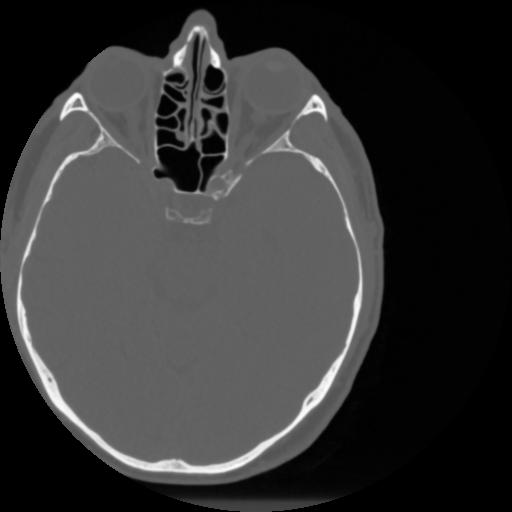

4 CEREBRO,,Vol,0.5,CEREBRO,,